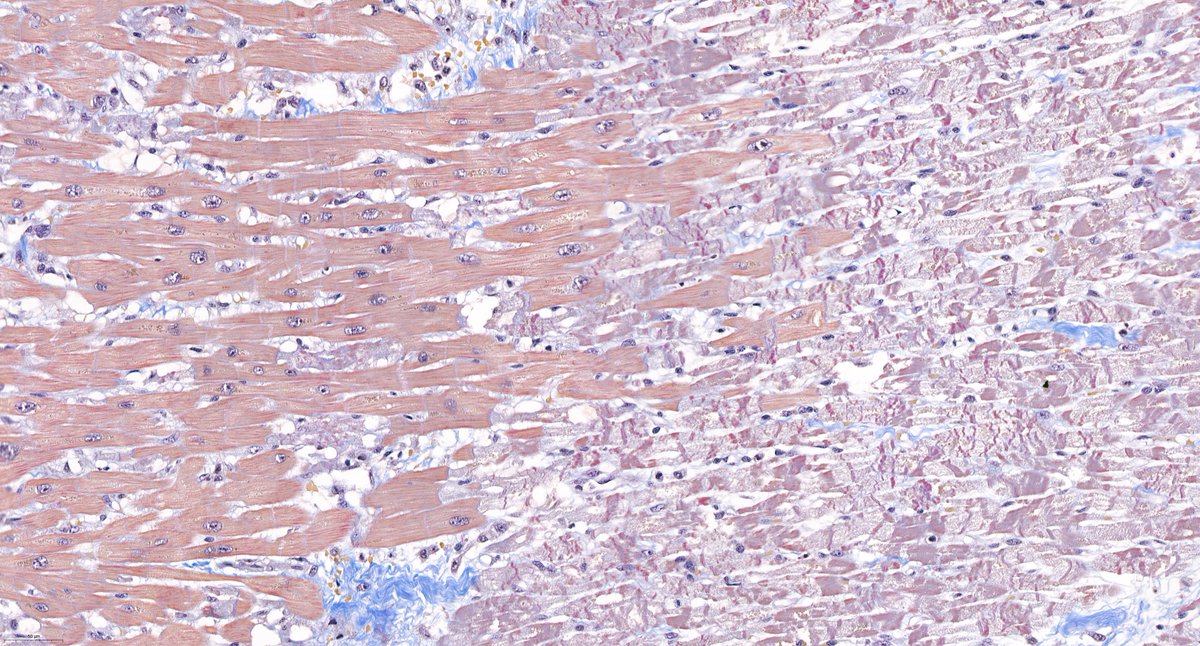

@goziemnweke @AmyHDeekenMD Acid Fuchsine Orange G - one of our favorites for renal pathology because it highlights connective tissue in blue and fibrin in bright red.